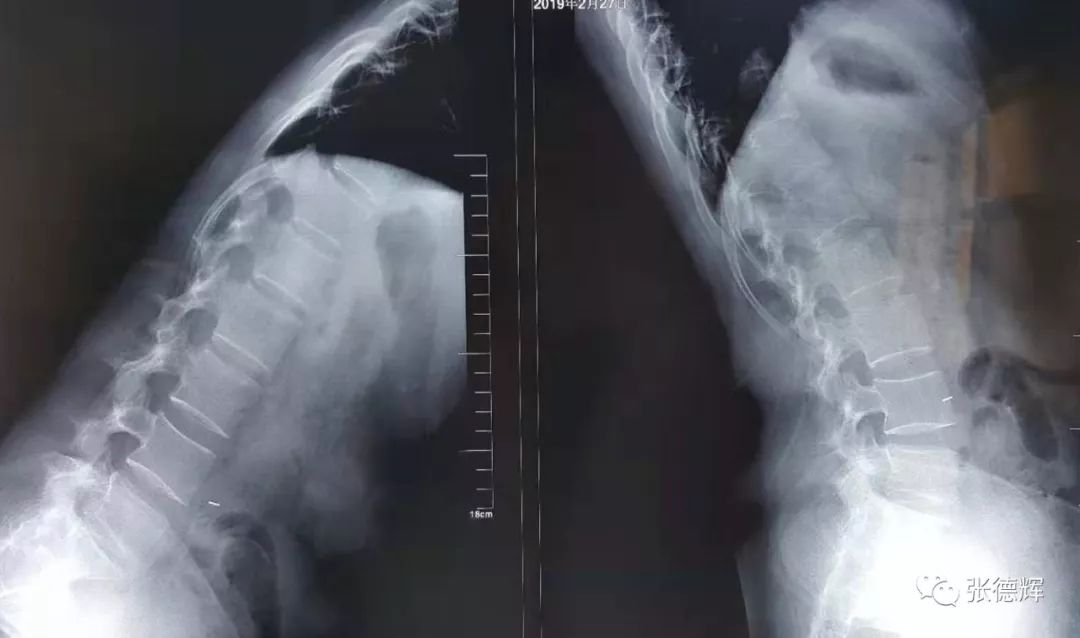

患者术前的各项影像检查

腰椎正侧位X光片及动力位片未见明显骨质结构异常及腰椎失稳